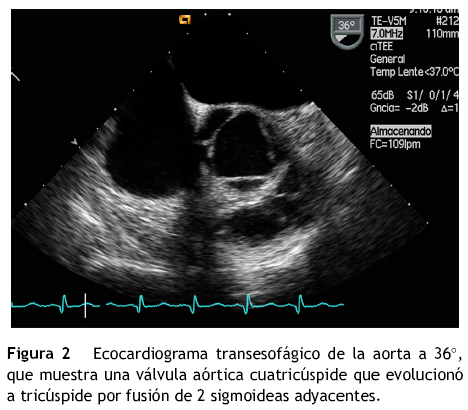

Quadricuspid Aortic Valve: Echocardiographic Diagnosis

Arq Bras Cardiol:imagem cardiovasc. 2013;26(4):341-345 343 Case Report Silva et al. Quadricuspid Aortic Valve: Echocardiographic Diagnosis Figure 3 - Imaging of quadricuspid aortic valve by transesophageal echocardiography - valve closure in cross or X. ... Read Document